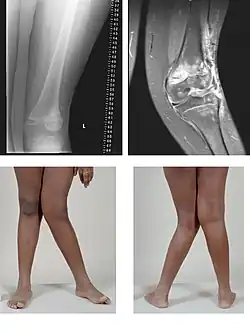

| Valgus deformity of the knee (genu valgum), seen in MRI and photograph | |

A valgus deformity is a condition in which the bone segment distal to a joint is angled outward, that is, angled laterally, away from the body's midline.[1] The opposite deformation, where the twist or angulation is directed medially, toward the center of the body, is called varus.

- Knee: genu valgum (from Latin genu = knee) – the tibia is turned outward in relation to the femur, resulting in a "knock-kneed" appearance. Common causes of knock-knee in adults include arthritis of the knee and traumatic injuries.